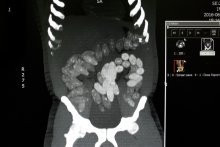

- Funkcjonariusze poddali podróżnego szczegółowej kontroli. Badania wykazały, że w jamie brzusznej mężczyzny może znajdować się kilkadziesiąt kapsułek. Jak się później okazało, było ich 90. Eksperci z laboratorium kryminalistycznego określili, że mamy do czynienia z 1,5 kg heroiny i kokainy – poinformowali Onet policjanci z KWP w Radomiu.